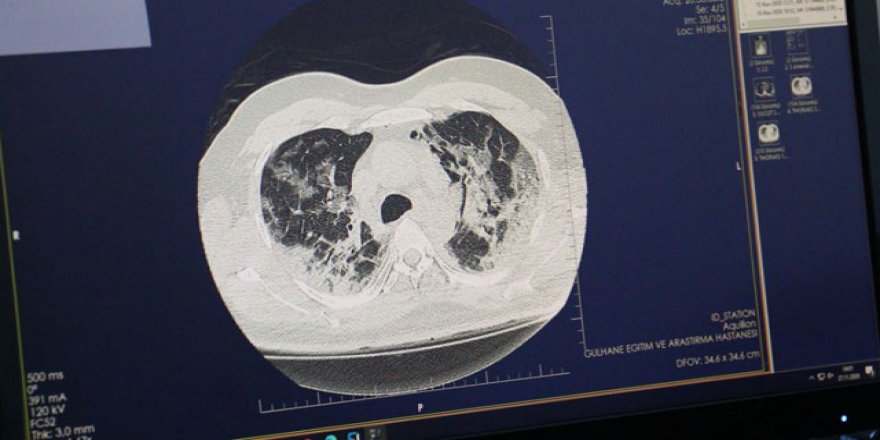

Sağlık Bakanlığı: Türkiye sigara kullanımında şampiyonluğa gidiyor!